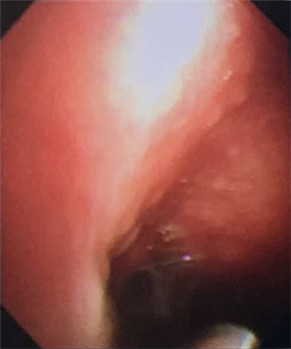

大量帶狀、網(wǎng)狀黏連帶

我院呼吸內(nèi)科采用改良型“軟式胸腔鏡”,該新設(shè)備軟硬結(jié)合,前端可彎曲,能多方向觀察胸腔內(nèi)改變,比老式“硬式胸腔鏡”的探查視野更大,診斷更準(zhǔn)確。